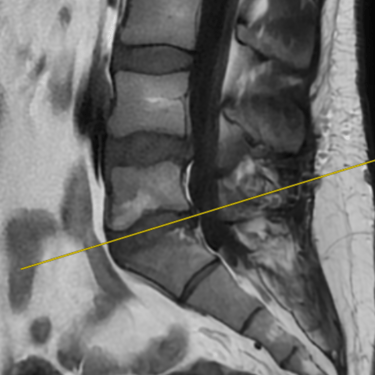

La discopatía degenerativa lumbar es una de las principales causas de dolor lumbar crónico. Se caracteriza por la pérdida de altura discal, deshidratación y cambios en las superficies vertebrales adyacentes. En la resonancia magnética (RMN) se identifican los cambios Modic, que reflejan alteraciones inflamatorias y degenerativas en el hueso subcondral: tipo I (edema), tipo II (grasa) y tipo III (esclerosis). Estos hallazgos permiten correlacionar el dolor lumbar con la patología discal y orientar un tratamiento personalizado. La RMN es, por tanto, una herramienta esencial para el diagnóstico preciso y la planificación terapéutica en pacientes con esta condición.